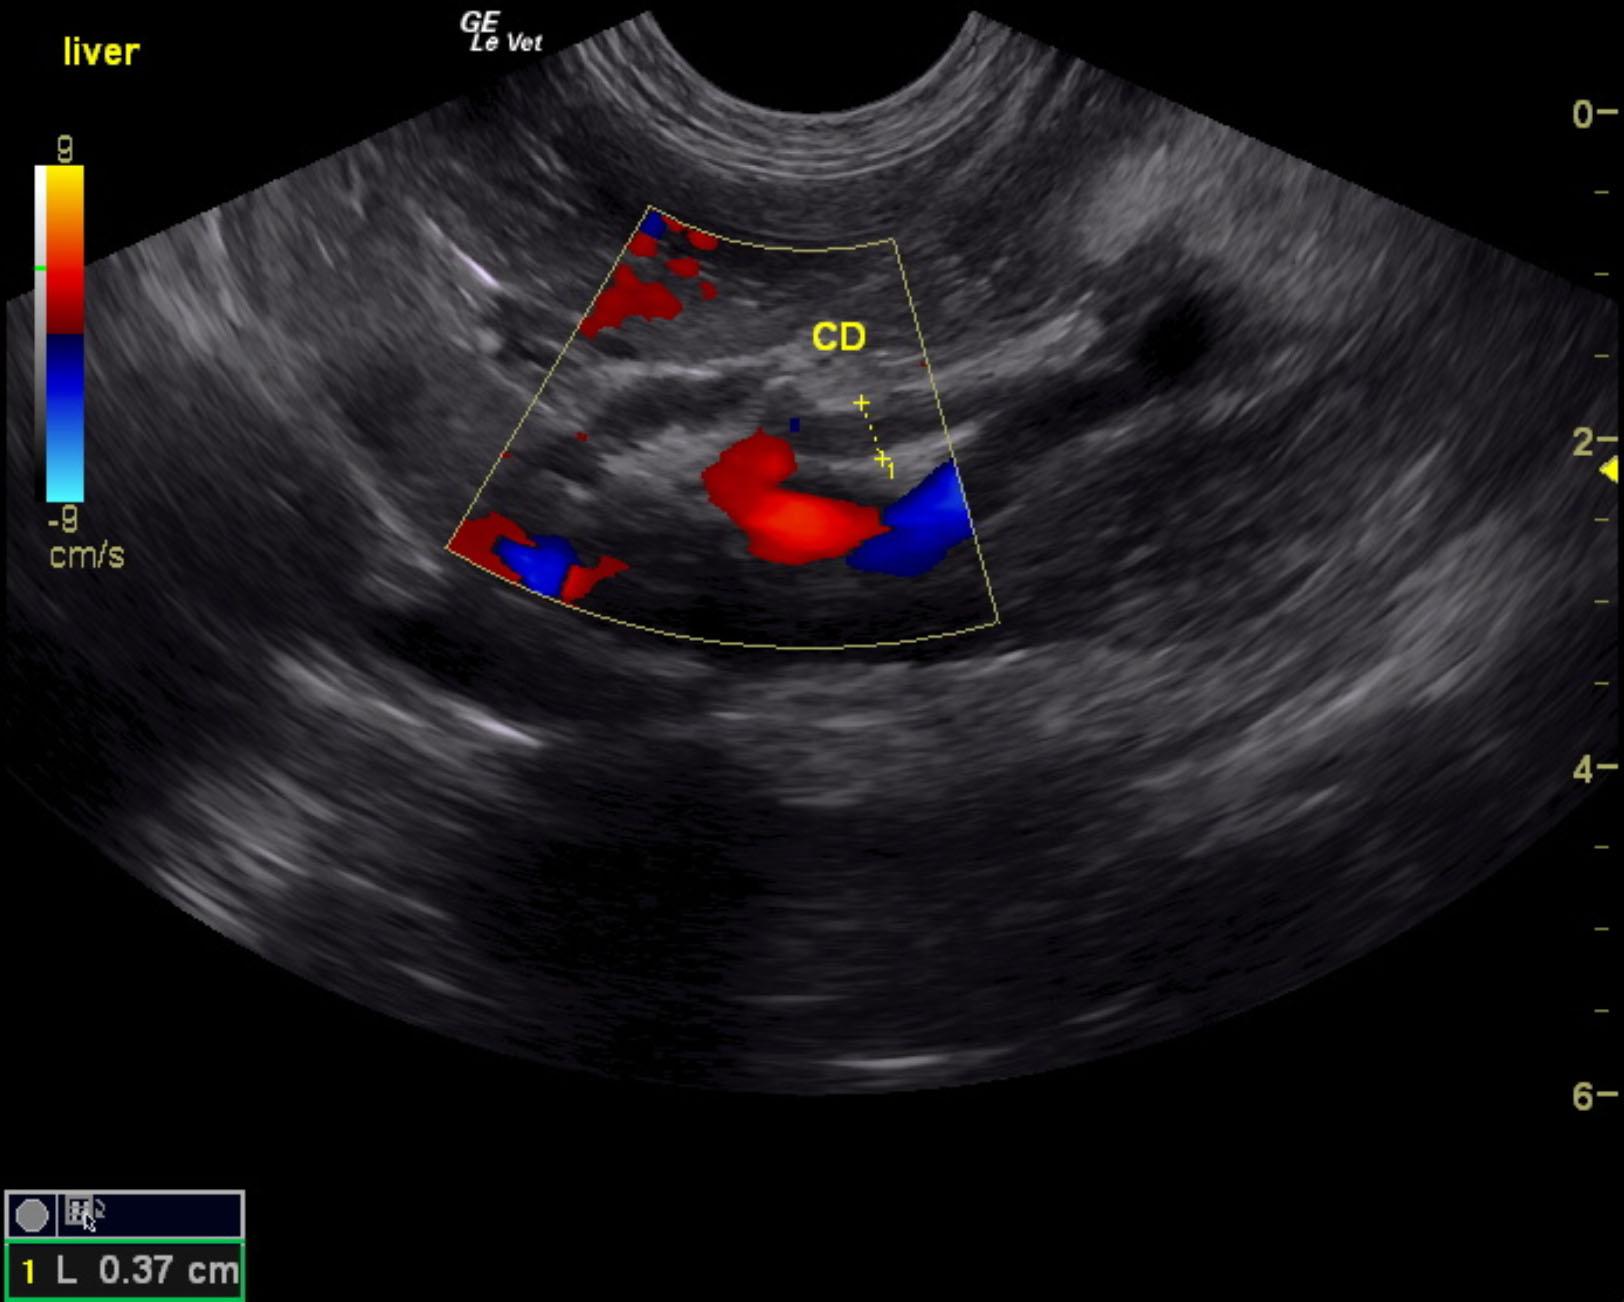

A 10-year-old female spayed DSH cat was presented for evaluation of intermittent diarrhea, weight loss, and anorexia. Blood work was unremarkable.

A 10-year-old female spayed DSH cat was presented for evaluation of intermittent diarrhea, weight loss, and anorexia. Blood work was unremarkable.